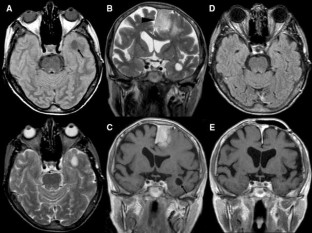

Fig. 3

Patient 1 was a 76-year-old woman with right hemiparesis and aphasia from a left cranial vault meningioma infiltrating the superior sagittal sinus, and a left temporal lobe giant perivascular space. Patient 2 was a 70-year-old man with pituitary apoplexy, vasospasm, cerebral ischemia, and two dPVSs, one in the right temporal lobe, and one in the left anterior perforate substance. Patient 3 was a 78-year-old man with a generalized seizure, and a right temporal lobe dPVS.

In all the patients, temporal lobe giant or dPVSs underwent regression, following meningioma subtotal resection (patient 1) or pituitary lesion shrinkage (patient 2), or spontaneously (patient 3). In patient 2, the left anterior perforate substance dPVS was unchanged.